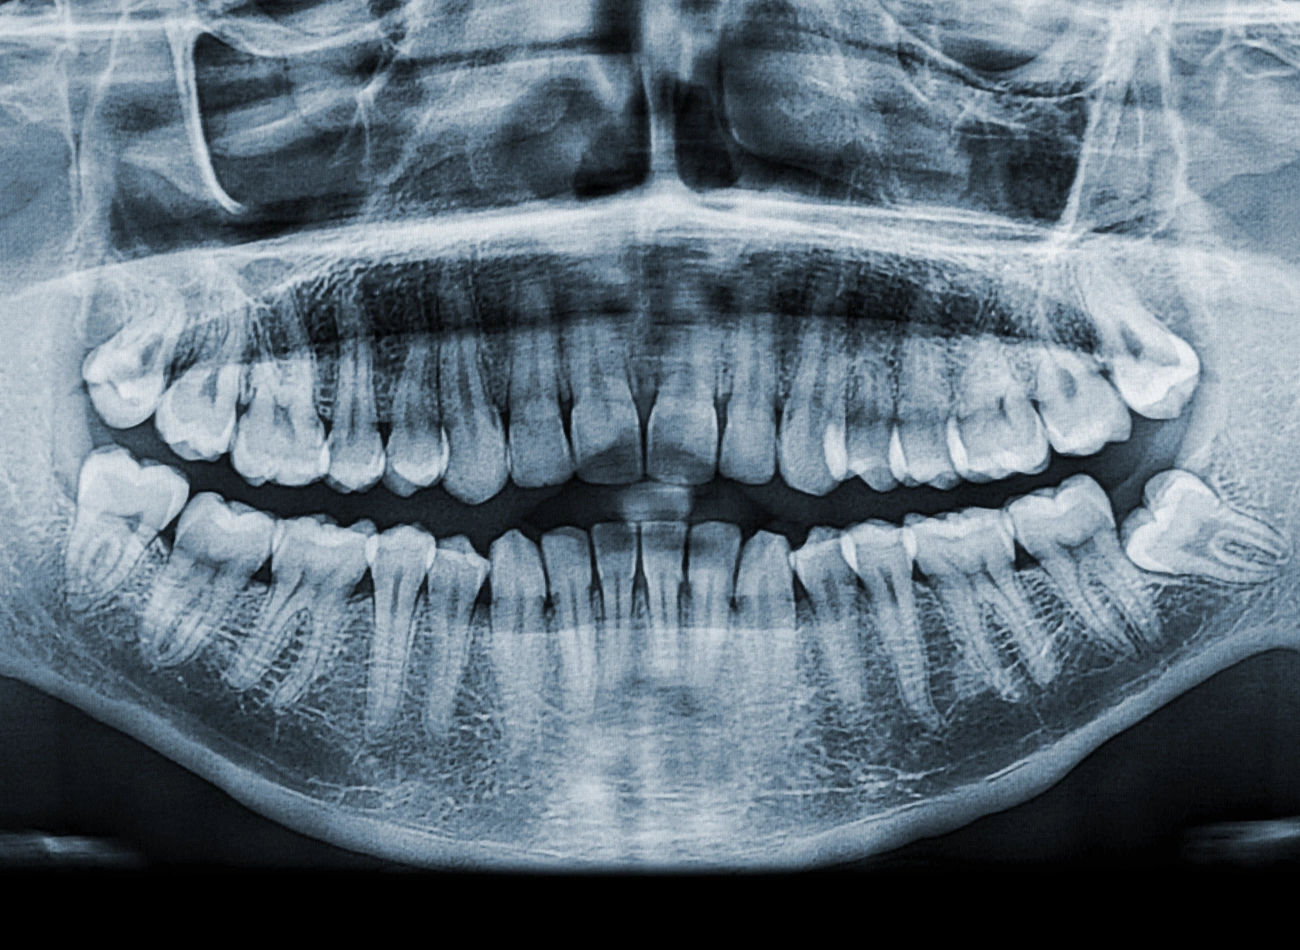

In der Fachzahnarztpraxis Implantologie Oralchirurgie Biberach haben wir die notwendige Erfahrung, um Weisheitszähne sicher, schnell und mit höchster Präzision zu entfernen. Vor dem Eingriff erstellen wir, falls nötig, ein dreidimensionales Röntgenbild mittels digitaler Volumentomographie (DVT), sodass die Lage des Zahns und seiner benachbarten anatomischen Strukturen exakt beurteilt werden kann.